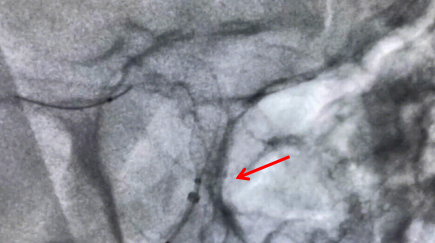

近日,重庆医科大学附属璧山医院(重庆市璧山区人民医院)呼吸介入团队成功为一名九旬高龄患者进行了高危肺结节微波消融术,术后恢复良好。